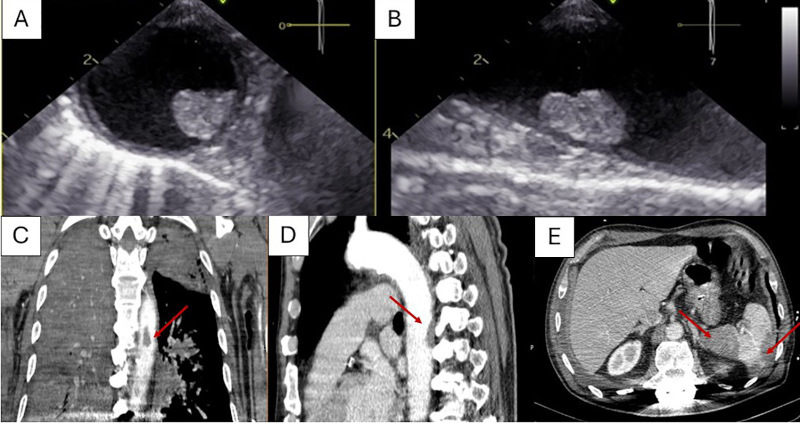

Transthoracic and transesophageal echocardiography (TEE) demonstrated preserved left ventricular systolic function with mid-basal inferoposterior hypokinesia, alongside severe, eccentric AMR, with pulmonary vein flow reversal, due to flail of the posterior mitral leaflet, involving P1-P2 scallops, consistent with probable posteromedial PMR (Figure 1C-F). A descending thoracic aortic atherosclerotic plaque with suspected mural thrombus was also noted, later confirmed with CT angiography, along with multiple splenic infarcts. (Fig.2).

Fig. 2

Transesophageal echocardiographic images of the descending thoracic aorta demonstrating an atherosclerotic plaque with suspected mural thrombus (A) short-axis view; (B) long-axis view. Contrast-enhanced chest CT scan in coronal (C) and sagittal (D) planes revealing an atherosclerotic plaque in the descending thoracic aorta with an adjacent non-enhancing area along the posterior wall, suggestive of a mural thrombus (arrows). Multiple splenic infarcts are also visible (E).